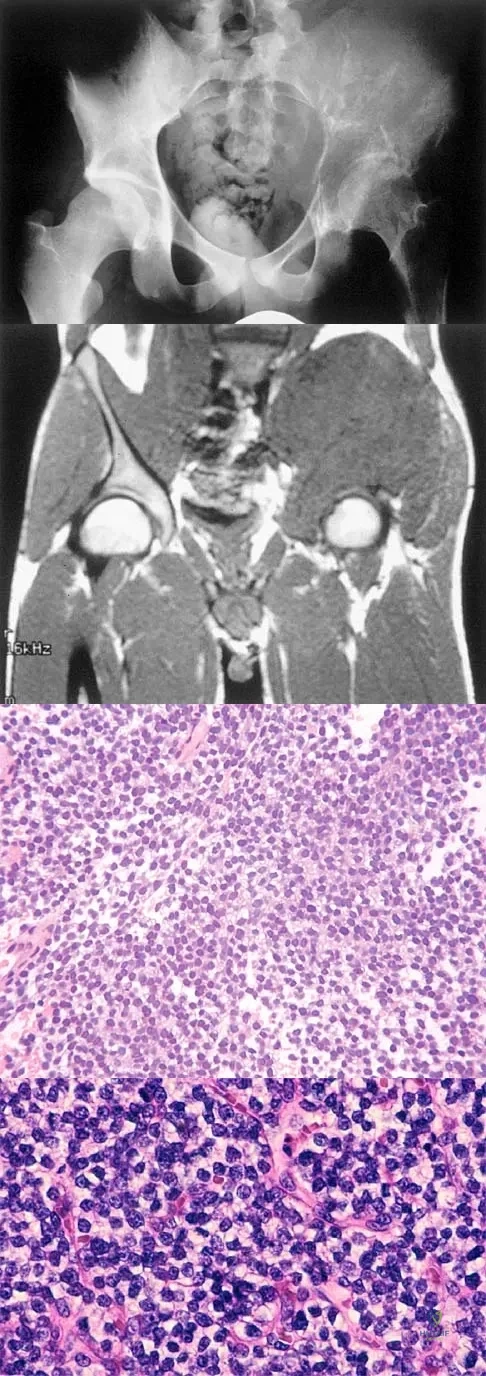

Question 28

A 25-year-old man has had an insidious onset of left hip pain over the past 11 months. A radiograph, coronal MRI scan, and histopathologic specimens are seen in Figures 2a through 2d. What is the most likely diagnosis?

Explanation